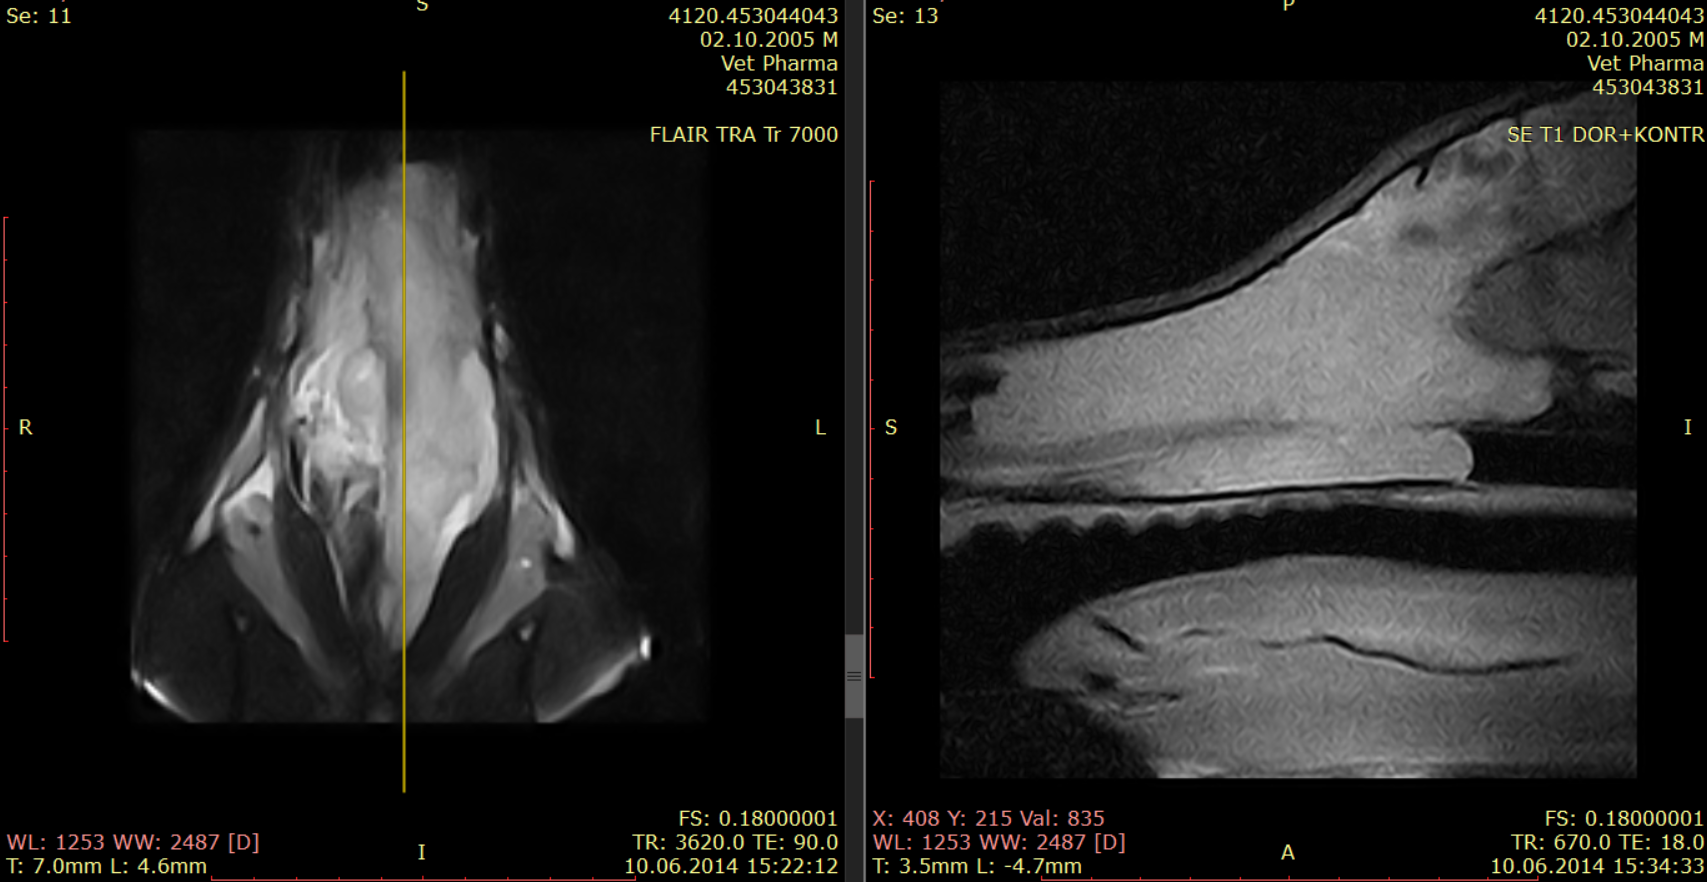

Магнитно-резонансная томография или компьютерная томография носовых ходов и придаточных пазух считаются золотым стандартом визуальной диагностики опухолей носовой полости. Для планирования лечения необходимо определить локализацию новообразования.

Объем новообразования и размер перифокального отека имеют значение для прогноза. Оценить по компьютерной томографии такие параметры, как размер новообразования и отек вокруг опухоли, нельзя.

Рис. 4. Программа FLAIR. Перифокальный отек обозначен стрелками, при этом объем новообразования на следующем рисунке 5 гораздо меньше (обозначено стрелками).Рис. 5. Программа T1 с контрастом.

Рис. 4. Программа FLAIR. Перифокальный отек обозначен стрелками, при этом объем новообразования на следующем рисунке 5 гораздо меньше (обозначено стрелками).Рис. 5. Программа T1 с контрастом.

Рис.6. Та же собака, что на рис. 5 и 4.

Рис.6. Та же собака, что на рис. 5 и 4.

Рис. 7.

Рис. 7.